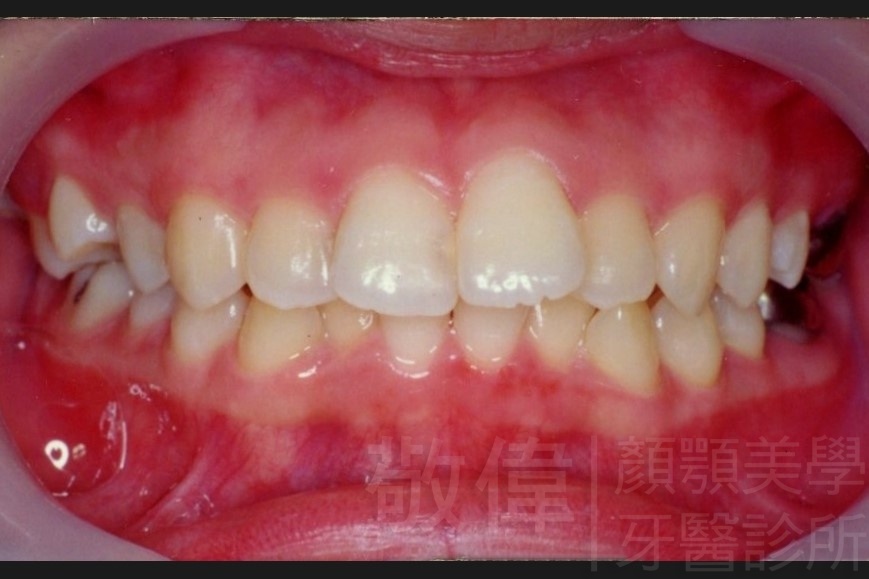

齒顏矯正/上下暴牙嘴唇不容易合起來

矯正前-右   矯正前-正   矯正前-左

矯正後-右   矯正後-正   矯正後-左

<個案說明>

上下暴牙嘴唇不容易合起來,經矯正完成後,嘴唇很容易合起來。在學生時期的時候的他,舉止之間充滿著有自信,當時還參加了舞蹈社團,充滿了多采多姿的生活。